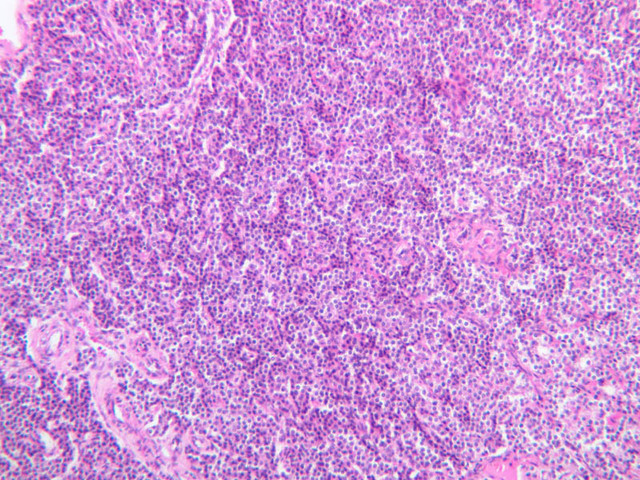

Examine slide B-56 (H&E [2.5x, 10x, 20x, 40x-labeled] [10x, 20x, 40x-labeled] [20x, 40x] [10x, 20x, 40x-labeled] [10x, 20x, 40x]). The connective tissue capsule of each parathyroid gland is continuous with that of the thyroid gland. It extends into the substance of the gland, dividing it into poorly defined lobules. Fat cells may separate the groups of cells and increase with age. Note the rich capillary network. The parenchyma is composed of two types of cells: (1) Principal or chief cells and (2) oxyphil cells. The polygonal chief cell is by far the more numerous cell type. Its nucleus is centrally located and has a vesicular chromatin pattern with a prominent nucleolus and its cytoplasm stains rather lightly. Oxyphil cells, which are less regular in shape and considerably larger than chief cells, are scattered singly or in small clusters. Their nuclei are smaller and more condensed than those of the chief cells and, owing to a very rich complement of mitochondria, their cytoplasm is distinctly acidophilic.